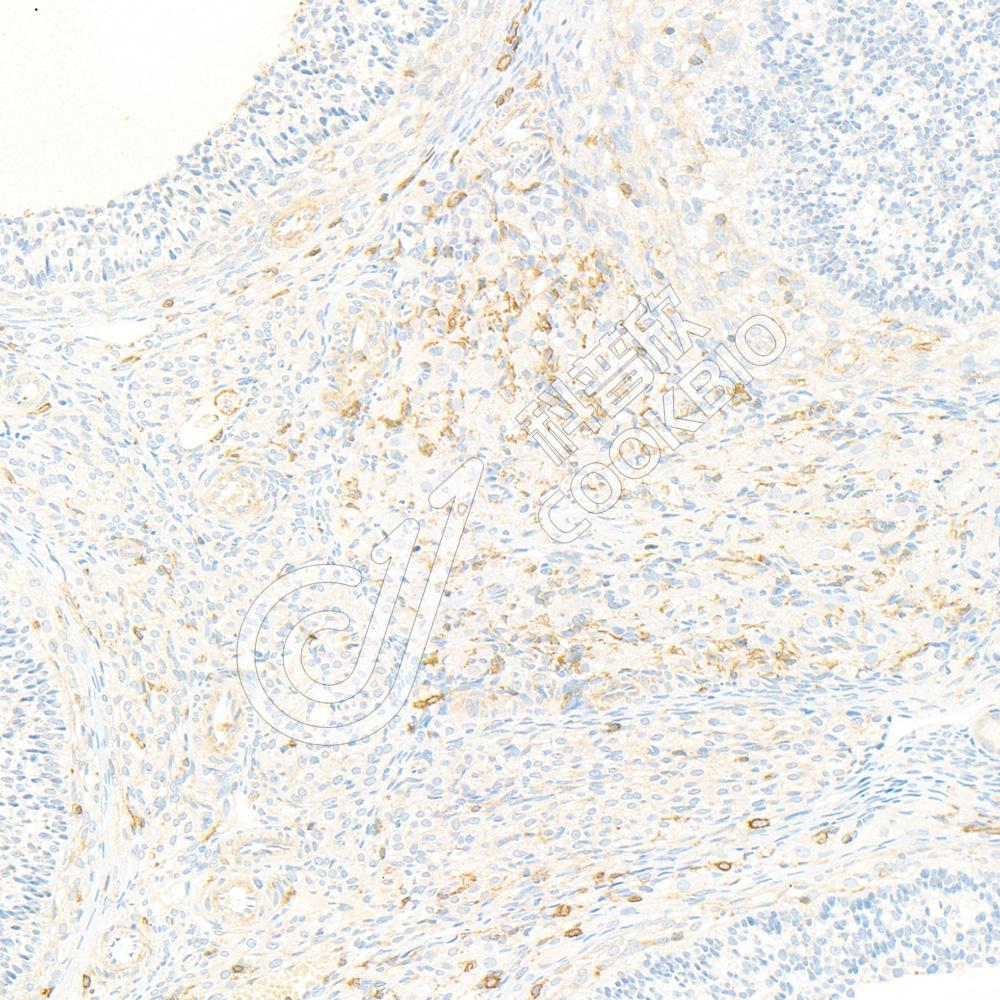

IHC检测NRK蛋白(货号 K135502).

样品: 小鼠骨骼肌, 4%多聚甲醛 (货号KSG1101) 固定12-24小时.

抗原修复: 柠檬酸抗原修复液(干粉, pH 6.0) (KSG1201), 98℃, 20分钟.

—抗: 1: 1900稀释, 4℃ 孵育过夜.

二抗: S-vision免疫组化多聚二抗(山羊抗兔),即用型 (货号KB3906), 室温孵育20分钟.

样品: 大鼠卵巢, 4%多聚甲醛 (货号KSG1101) 固定12-24小时.